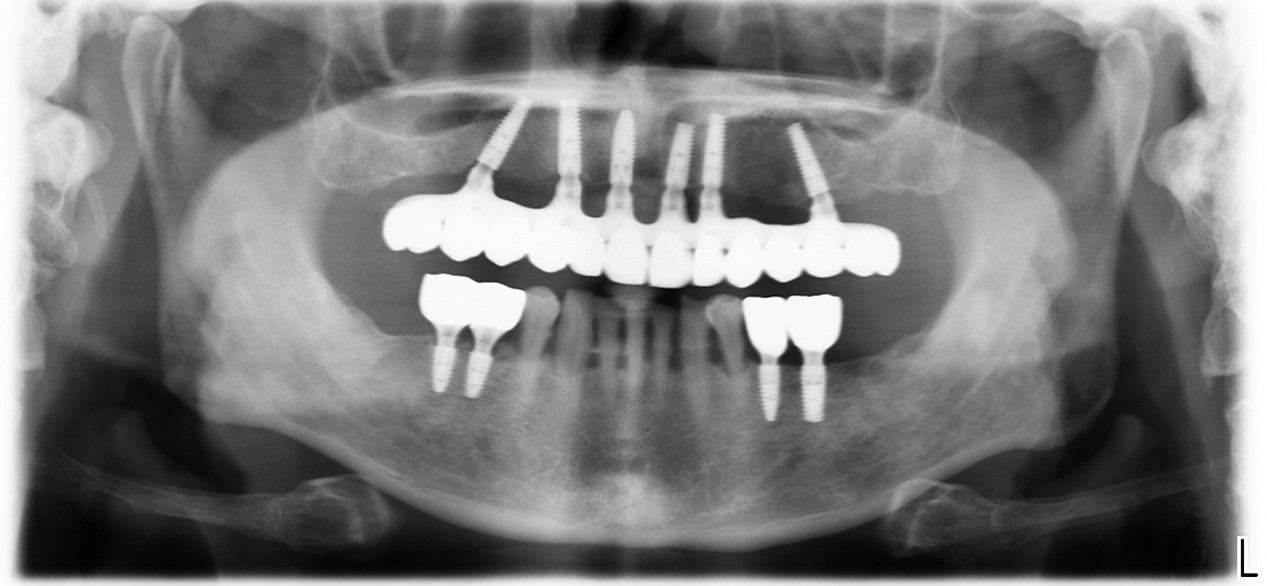

All on 4植牙重建

All on 4 (All on 4全口植牙) 是ㄧ種提供全口無牙的病患一個解決惱人活動假牙的治療方法。All on 4利用4顆特殊設計的植牙,將美觀、舒適的假牙牢牢地固定在上面。你在短短的幾天內,就可擁有你想要的牙齒,無需等待漫長的治療時期。